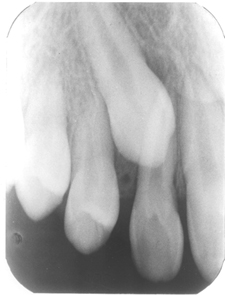

Normally, the maxillary cuspid teeth are the last of the “front” teeth to erupt into place. They usually come into place around age 13 and cause any space left between the upper front teeth to close together. If a cuspid tooth gets impacted, every effort should be made for it to erupt into its proper position in the dental arch. The techniques involved to aid eruption can be applied to any impacted tooth in the upper or lower jaw, but most commonly they are applied to the maxillary cuspid (upper eye) teeth. Most often these impacted eyeteeth are located on the palatal (roof of the mouth) side of the dental arch. The remaining impacted cuspid teeth are found in the middle of the supporting bone but stuck in an elevated position above the roots of the adjacent teeth or out to the facial side of the dental arch.

The older the patient, the more likely an impacted tooth will not erupt by nature’s forces alone, even if the space is available for the tooth to fit in the dental arch. The American Association of Orthodontists recommends that a panorex screening x-ray, along with a dental examination, be performed on all dental patients at around the age of seven years to count the teeth and determine if there are problems with eruption of the adult teeth. It is important to determine whether all the adult teeth are present or are some adult teeth missing, as well as extra teeth present or unusual growths that are blocking the eruption of the tooth. If there is extreme crowding or too little space available an eruption problem may exist. This exam is usually performed by your general dentist or hygienist who will refer you to an orthodontist if a problem is identified. Treating such a problem may involve an orthodontist placing braces to open spaces to allow for proper eruption of the adult teeth. Treatment may also require referral to an oral surgeon for extraction of over-retained baby teeth and/or selected adult teeth that are blocking the eruption of the all-important cuspids, or eyeteeth. The oral surgeon will also need to remove any extra teeth (supernumerary teeth) or growths that are blocking eruption of any of the adult teeth. If the eruption path is cleared and the space is opened up at an early age, there is a good chance the impacted eyetooth will erupt with nature’s help alone. If the cuspid tooth is allowed to develop too much, the impacted tooth will not erupt by itself even with the space is available. If the patient is too old, there is a much higher chance the tooth will be fused in position. In these cases the tooth will not budge despite the efforts of the orthodontist and oral surgeon to erupt it into place. Sadly, the only option at this point is to extract the impacted tooth and consider an alternate treatment to replace it in the dental arch.

In cases where the cuspid will not erupt spontaneously, the orthodontist and oral surgeon work together to get these unerupted cuspid to erupt. Each case must be evaluated on an individual basis but treatment will usually involve a combined effort between the orthodontist and the oral surgeon. The most common scenario will call for the orthodontist to place braces on the teeth. A space will be opened to provide room for the impacted tooth to be moved into its proper position in the dental arch. If the corresponding baby tooth has not fallen out already, it is usually left in place until the space for the adult tooth is ready. Once the space is ready, the orthodontist will refer the patient to the oral surgeon to have the impacted cuspid exposed and bracketed.